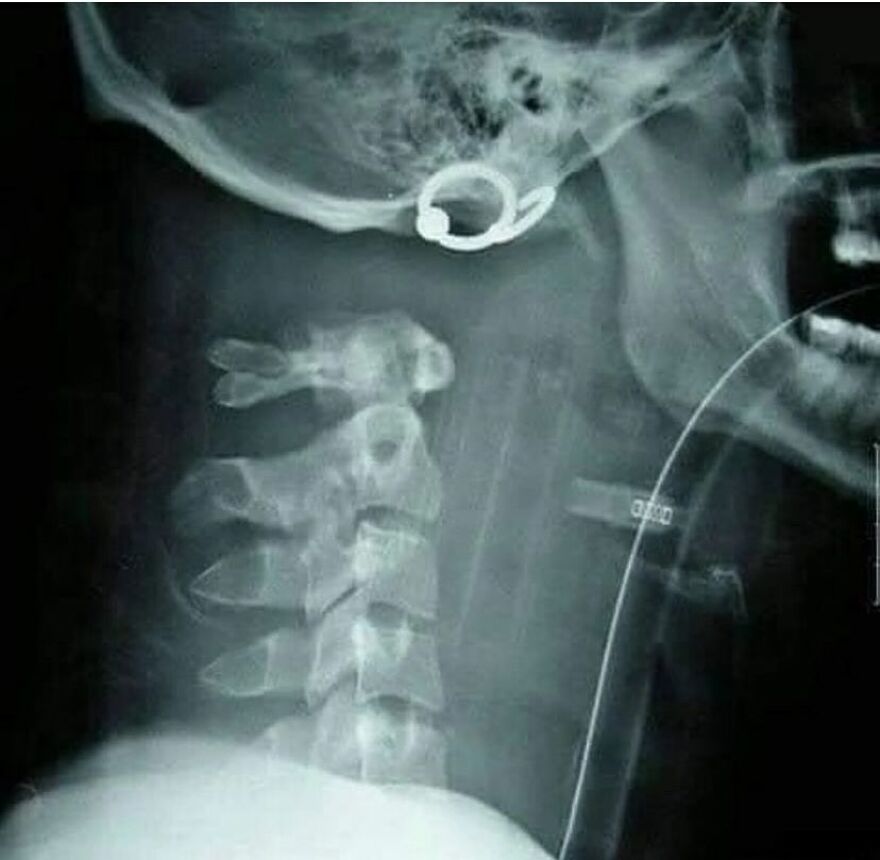

A 15-year-old boy has three extra vertebrae in his neck - a condition known as supernumerary vertebra along with congenital scoliosis - causing pain, stress on his nerves, and making it difficult for him to walk.